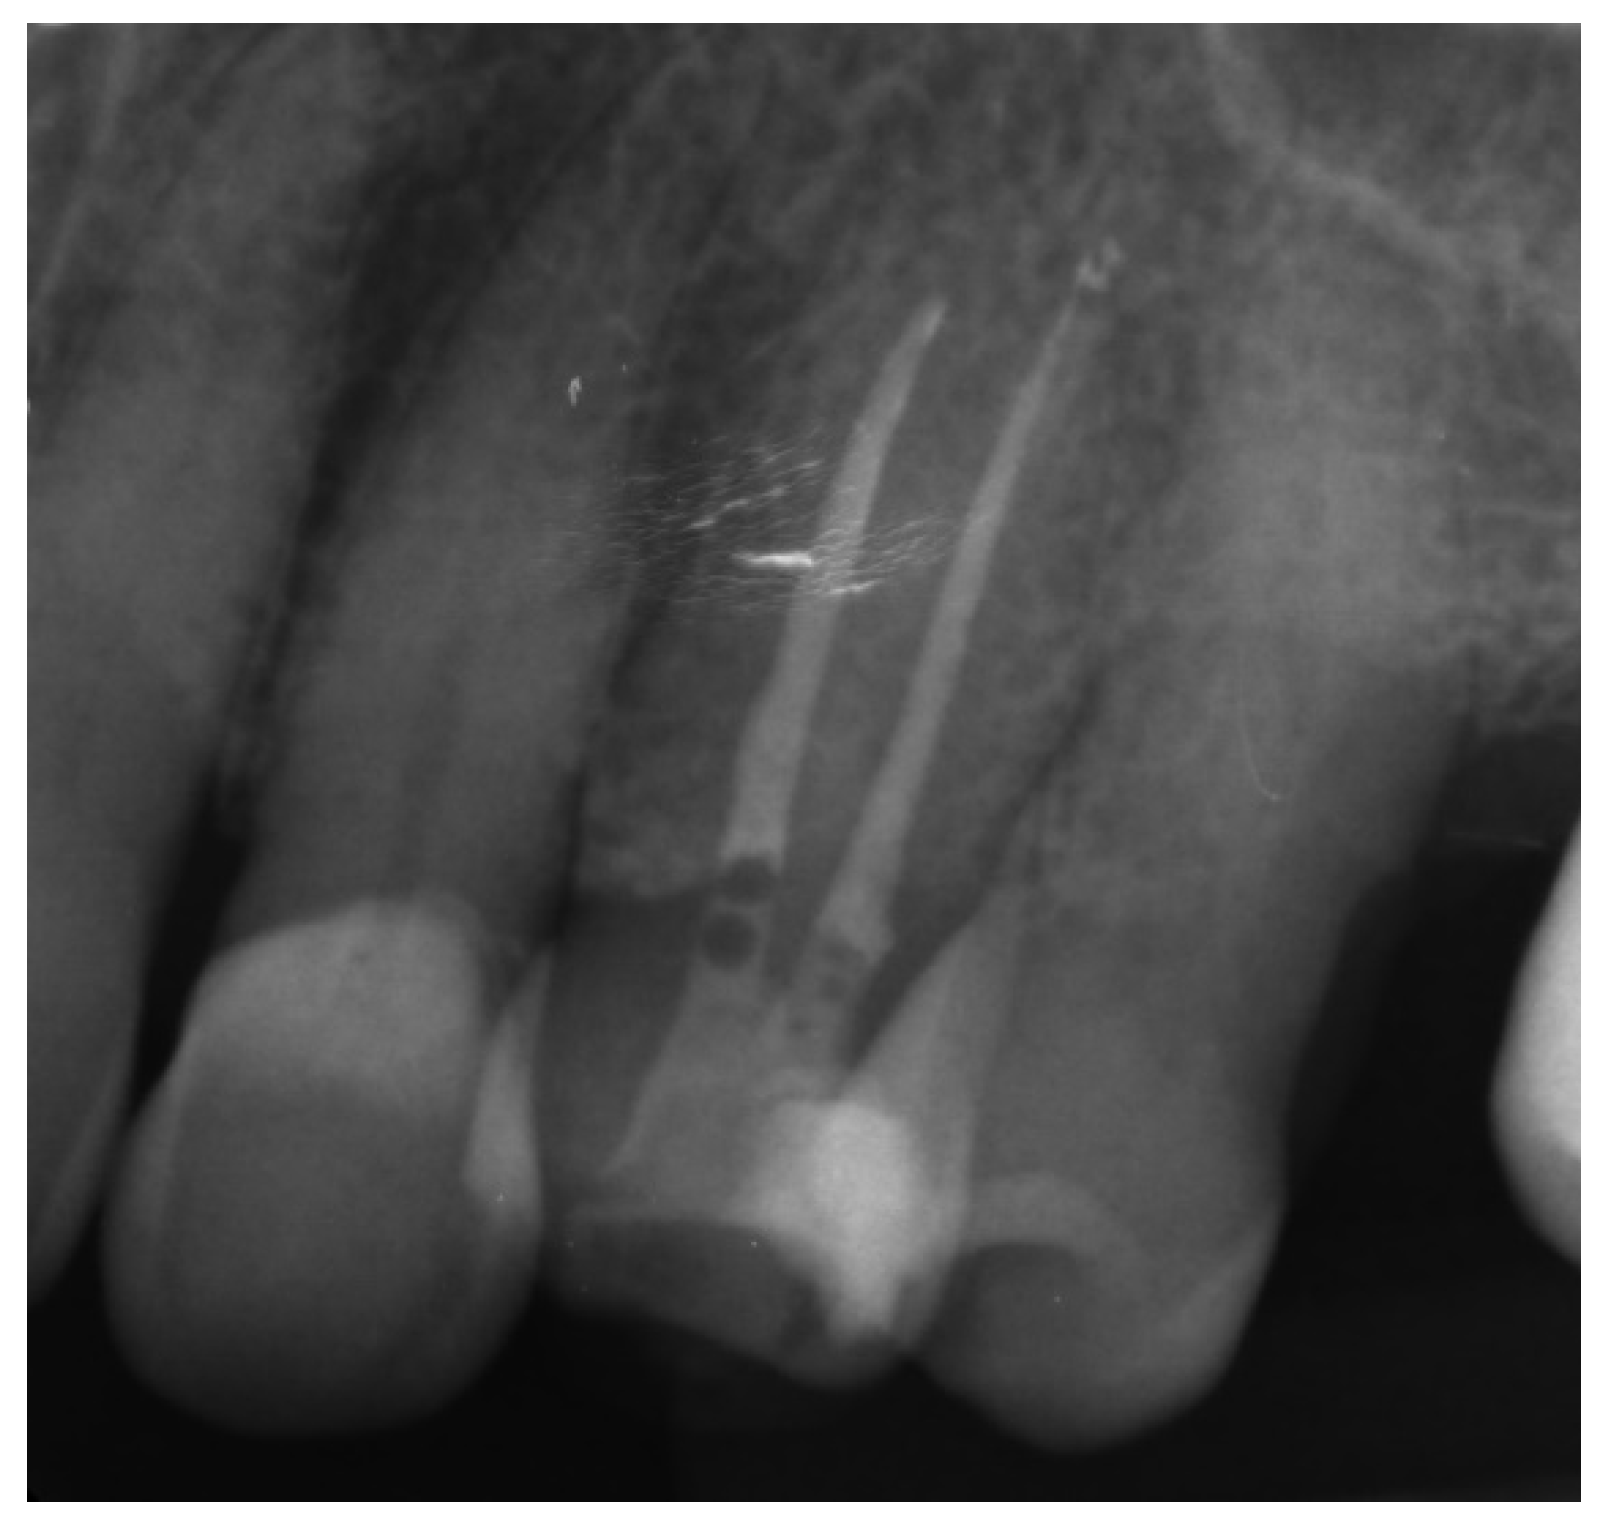

Canal Treatment

The correct fit of the guide was verified before and after the rubber dam was placed. For local anaesthesia, 1.7 mL Ubistesin forte (3 M ESPE, Seefeld, Germany) was administered (articaini hydrochloridum 40 mg + epinephrine hydrochloridum 0.012/1 mL). A small sign was made on the enamel surface through the guide to indicate the access point. The enamel was removed in a minimally invasive manner with a diamond bur until the dentine was exposed. The guide was placed on the teeth and the treatment was performed with Munce Discovery Bur #1 (CJM Engineering, Santa Barbara, CA, USA) with a speed of 10,000 rpm. This bur was a round carbide bur with a head diameter of 0.8 mm (ISO head size 08) and a total length of between 31 and 34 mm. The guide was removed every 2 mm to rinse the cavity, control endodontic access using an optical microscope, and clean the bur. After the bur reached the estimated depth, the C-Pilot #10 and #15 files (VDW, Munich, Germany) were used to check the canal position. Radiographic examination was performed to confirm correct canal access (Figure 15). The canal was reached at a length of 22 mm from the top of the guide sleeve - 1 mm deeper than the virtually planned depth. Once the remaining canal was reached, the length was confirmed with an electronic apex locator (Raypex 6; VDW, Munich, Germany). A conventional root canal treatment followed. The canal was irrigated with 5.25% sodium hypochlorite (NaOCl), including passive ultrasonic activation, and instrumented with ProTaper Gold (Dentsply Sirona Endodontics, Ballaigues, Switzerland) up to the F3 file size (0.30/0.09v). It was dried with paper points and obturated with vertically condensed gutta-percha and epoxy sealer (AH Plus, De Trey, Konstanz, Germany). The access cavity was cleaned and filled with a composite resin (Estelite Asteria, Tokuyama Dental Corporation, Tokyo, Japan).

Figure 15. Radiographic examination was used to confirm (a) correct path of access pathway during procedure and (b) correct root canal access; (c) post-obturation radiograph.